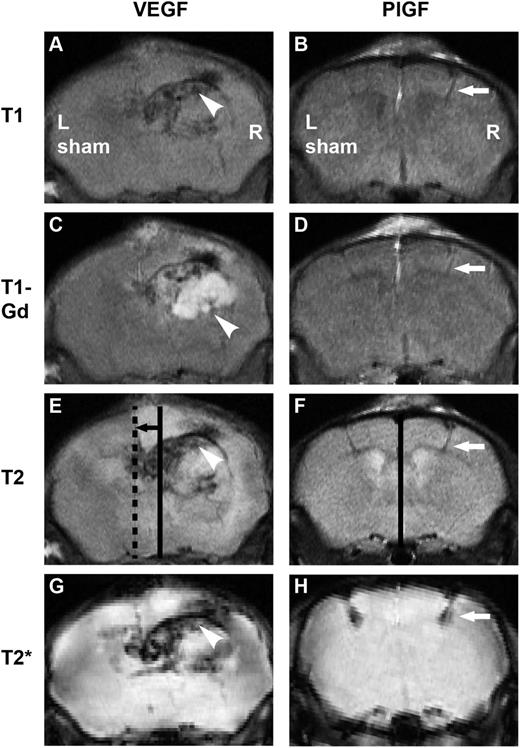

Two weeks after right-sided vascular growth factor and left-sided sham injections, the mice were analyzed by MRI of the brain (Figure 7). VEGF treatment led to an expansive hemangioma and severe, whole-hemispheric edema, causing a major distortion of anatomical structures and a brain midline shift in the T1 sequence. Such severe midline shift and subfalcine herniation is life-threatening. Gadolinium-based contrast agents, routinely used in human diagnostics, give signal enhancement at the sites of BBB disruption.31 Hyperintense enhancement (T1-Gd series, white) revealed the breakdown of the BBB in a strikingly wide region around the VEGF transduction site and the T2 series demonstrated hyperintensity (white) over the majority of the hemisphere, indicating severe edema throughout the hemisphere. The T2* series revealed the extravasation of blood as a hypointense (black) area, showing a large area of microhemorrhages after the VEGF treatment. On the contrary, PlGF transduction did not induce edema or significant BBB breakdown, and the anatomical structures remained intact. Only the injection needle path was detectable as a minor site of extravasation, best visible as hypointesity (black) in the T2* series.

In vivo effects of VEGF and PlGF visualized by MRI. Right-sided growth factor injections were performed accompanied by left-sided sham operation. Incubation time: 2 weeks. (A) After VEGF gene transfer, the macroanatomy of the brain is distorted as observed in T1 images, (C) the BBB is disintegrated from a large area seen as enhancement (white) on T1-Gd series, (E, continuous line: anatomical midline, dashed line: actual midline, black arrow: brain shift) T2 sequence shows major edema (white) with brain shift, and T2* demonstrates hemorrhage (black). Arrowheads point to a hemangioma. Note that after PlGF treatment, (B) the macroanatomy is intact, (D) enhancement is minimal, (F, continuous line: anatomical and actual midline coincide) there is no edema and no brain shift, and (H) minor hemorrhage is only seen at injection path. White arrows point to injection path.